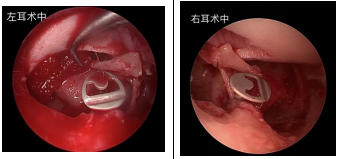

患者王某,女,54岁,因“反复双耳流脓伴听力下降10余年”自行佩戴助听器入院,入院诊断双侧慢性中耳炎,术前听力提示双侧传导性聋,气骨导差约40dB。为确保手术成功开展,我院耳鼻喉科团队对患者的病情进行了全面评估,完善相关专业检查,为患者制定了一套完善的手术治疗方案。双耳分两次行耳内镜下鼓室成形术+人工听骨链重建术,手术顺利,术后1月复查双耳鼓膜完整,听力图提示气骨导差约15dB-20dB,患者听力明显改善,已摘除助听器。

术中置入人工听骨PORP

小结:人工听骨链重建术可显著改善传导性耳聋听力,而耳内镜手术相对显微镜耳科显微手术更微创,越过狭窄区域在深处提供广角高清的手术视野,术中无显露切口、磨骨量少,具有创伤小、术后恢复快等优点。